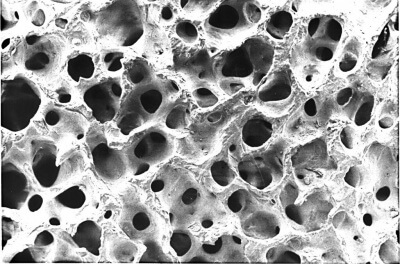

Костно-пластические материалы для имплантологии: подробный обзор